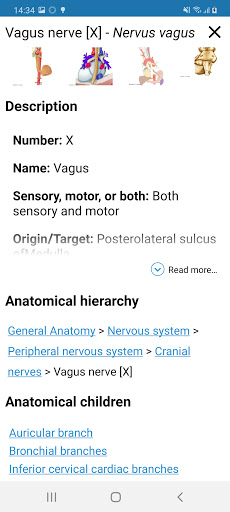

-In the details view of an anatomical structure related terms are now displayed

*Browse between anatomical parts using description links

* Introduced tables in anatomical structures definitions for better data structuring